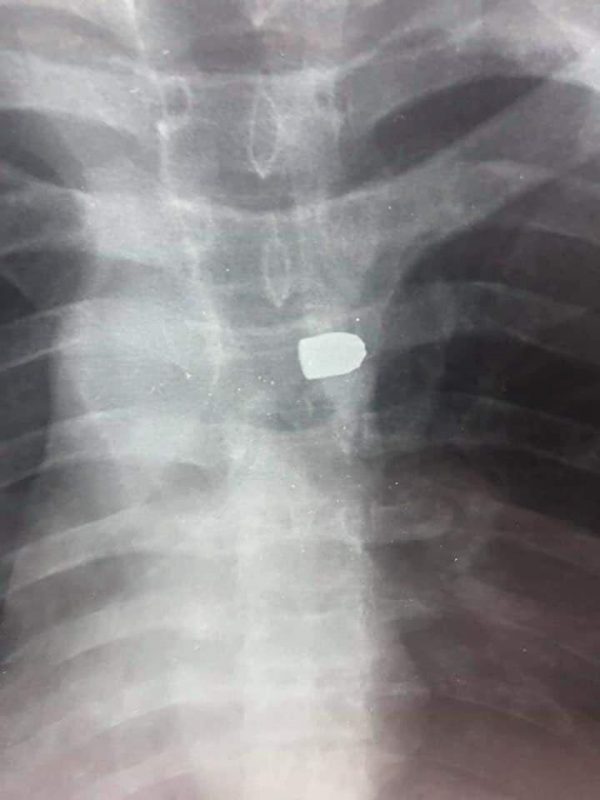

យ៉ាងនេះក្តី លោក អេង ហ៊ី ថ្លែងការពារកម្លាំងកងរាជអាវុធហត្ថខេត្តព្រះសីហនុថា ចំពោះក្បាលគ្រាប់ ដែលបាញ់ត្រូវជនរងគ្រោះនោះ គឺជាប្រភេទអាវុធខ្លីម៉ាកកា៥៩ ។ ហើយថា ចុងគ្រាប់ ដែលបានវះយកចេញពីខ្លួនជនរងគ្រោះ គឺជាប្រភេទចុងគ្រាប់កែច្នៃ។ ចំណែកអាវុធខ្លីចំនួន៦ដើម របស់កងរាជអាវុធហត្ថ លោក អេង ហ៊ី អះអាងថា នៅពេលកម្លាំងជំនាញបានយកទៅបាញ់ធ្វើតេស្តរកក្បាលគ្រាប់ និងបានយកក្បាលគ្រាប់ទៅកោសល្យវិច័យ គឺពុំមានលក្ខណៈ ដូចគ្នាក្បាលគ្រាប់ ដែលបាញ់ត្រូវជនរងគ្រោះនោះទេ ហើយគ្រាប់ ដែលបាញ់ត្រូវជនរងគ្រោះ គឺជាប្រភេទក្បាលគ្រាប់អាវុធខ្លីម៉ាក កា៥៩កែឆ្នៃ។ ចំណុចនេះ លោក អេង ហ៊ី ថ្លែងបដិសេធន៍ថា “គ្រាប់កាំភ្លើងដែលត្រូវជនរងគ្រោះនោះ គឺមិនមែនបាញ់ចេញពីកាណុងកាំភ្លើង របស់កម្លាំងកងរាជអាវុធហត្ថខេត្តព្រះសីហនុនោះទេ “។

លោក អេង ហ៊ី បានឲ្យដឹងដែរថា ជនរងគ្រោះដែលត្រូវគ្រាប់កាំភ្លើង ហើយកំពុងសម្រាកព្យាបាល ជំងឺនៅមន្ទីរពេទ្យនោះ ពេលនេះបានធូរស្បើយខ្លះៗហើយ ប៉ុន្តែអវៈយវៈផ្នែកខាងក្រោម របស់ជនរងគ្រោះ មិនទាន់អាចធ្វើចលនាបានទេ។ ហើយថា ករណីនេះក្រុមគ្រូពេទ្យកំពុងបន្តយកចិត្តទុកដាក់ក្នុងការព្យាបាលជនរងគ្រោះ។